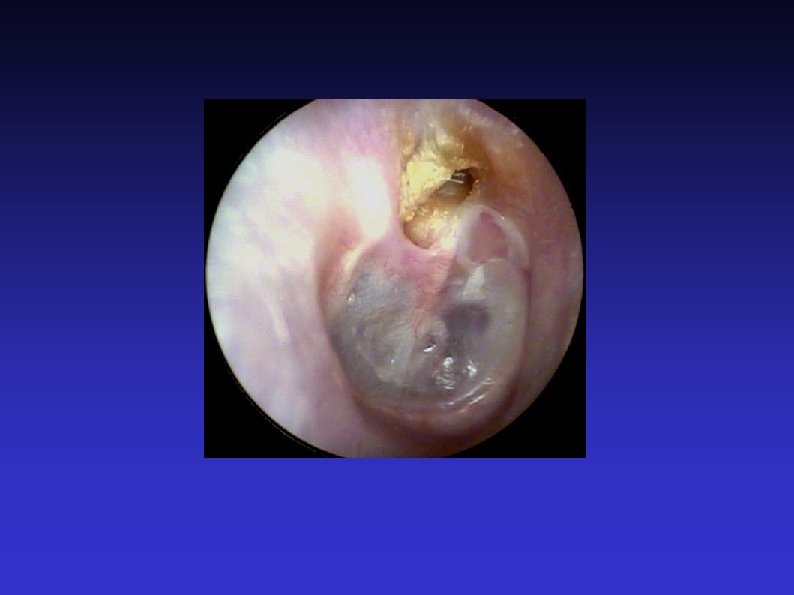

Examination of the Ear 7) Otoscopic examination The lateral process and handle of the malleus lie towards the centre of the tympanic membrane Four quadrants Perforation Central or marginal What can be seen through it Mastoid cavity Dry Wet, inflamed

Examination of the Ear 8) Fistula test A test for ENT doctors! Warn the patient A cholesteatoma has erroded part of a semi-circular canal Pressure in the EAM causes conjugate deviation of the eyes